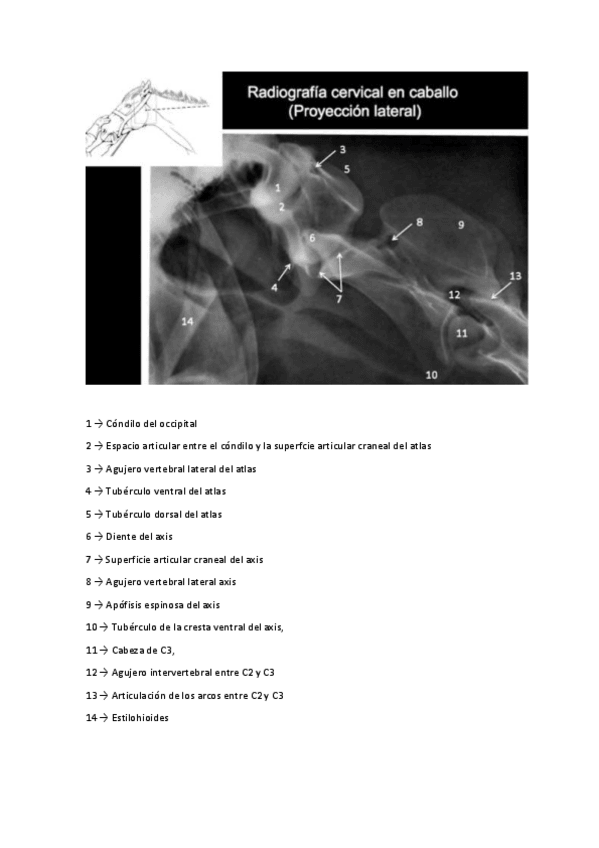

He publicado nuevos practicas de 1º EMBRIOLOGÍA Y ANATOMÍA I: Radiografias-Practica-2-Anatomia-cervicales.pdf

8 páginas